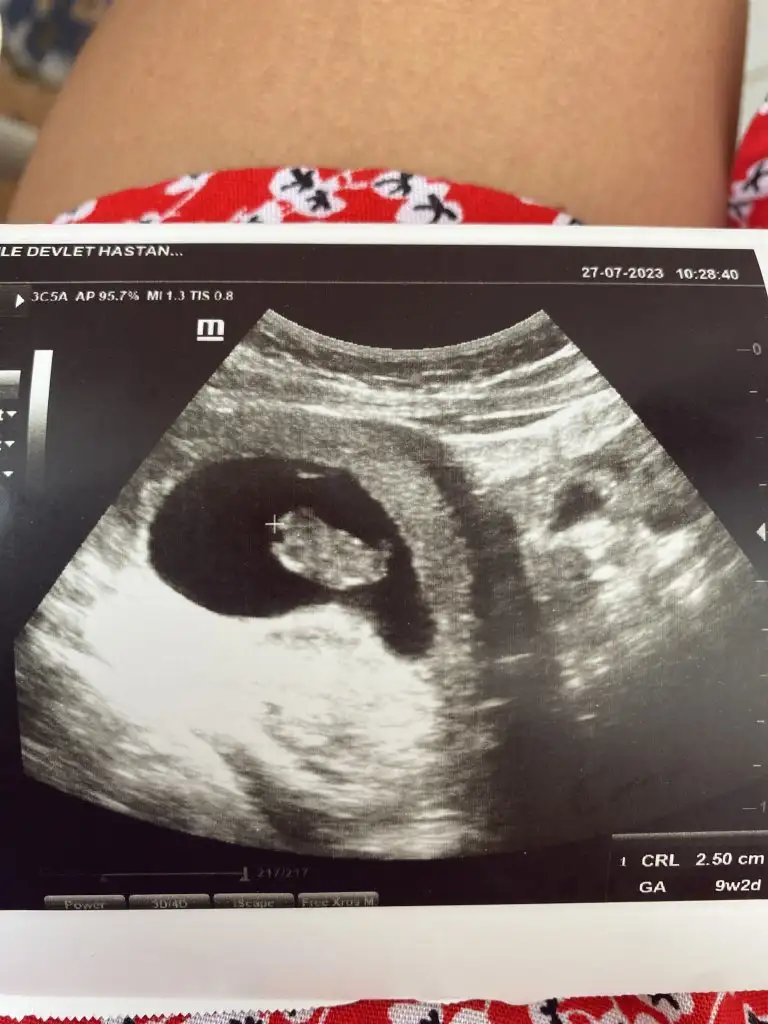

Banada tahminde bulunabılırmisiniz lütfen❤️💓💙bastakıler 9+2 sondaki 10+4